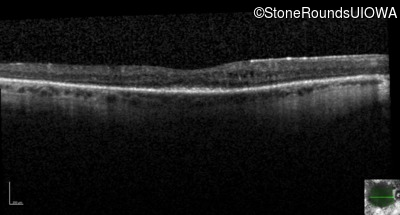

Optical Coherence Tomography - Right - 20/25 -1

Exemplar / OCT Stack

OCT Stack